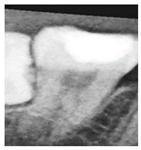

In the framing adjustment step, the central point of the oral structure was first identified. This point corresponded to the vertex of a second-order polynomial curve. The gap between the upper and lower jaws was then modeled using a quadratic curve that passes through the central point and connects to two boundary points on the image frame [21], as described by Equation (1). The resulting second-order curve used to represent the jaw separation is shown in Figure 4.

Figure 4. The result of the curve and central point are labeled. The red line indicates the boundary between the upper and lower jaws (maxilla and mandible) in this study.